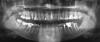

Gammy Опубликовано 30 ноября, 2012 Поделиться Опубликовано 30 ноября, 2012 Посоветуйте, что делать с левыми нижними 5-7? 7ка: можно ли восстанавливать коронкой со штифтом?Понимаю, что вкладкау бы надо, но очень боюсь, если что не то, то не перелечить (каналы запломбированы только 2 месяца назад).6ка: воспаление, но в том канале штифт (лечилась 3,5 года назад). Боль бывает иногда, но не в зубе, а как бы в челюсти, я не знала из-за чего до этого снимка. Варианты врачей: 1. удалять, 2. перелечивать, 3. контролировать снимком, т.к если не получится перелечить, только удаление. Какой более верный? (честно говоря, мне 3ий нравится).5ка: на имеющийся штифт коронку можно? перелечивать страшно Есть ли смысл тянуть с 7кой (например, временную коронку сделать), до окончательного решения проблемы с 6кой? (а то как бы мост не пришлось ставить). Ссылка на комментарий

IvanK Опубликовано 30 ноября, 2012 Поделиться Опубликовано 30 ноября, 2012 За терапевтов не скажу, но верхние 8ки удалять Ссылка на комментарий

dok1 Опубликовано 1 декабря, 2012 Поделиться Опубликовано 1 декабря, 2012 Перелечивать, и чем скорее, тем лучше. Не торопитесь в процессе, не подгоняйте врача. Ставьте постоянные пломбы и наблюдайте несколько месяцев. Но потом обязательно вкладки и коронки. Примерно такой вариант. 1 Ссылка на комментарий

Gammy Опубликовано 2 декабря, 2012 Автор Поделиться Опубликовано 2 декабря, 2012 про 8ки знаю А из 6ки штифт реально достать? Один врач посмотрел снимок и сказал не достанет. Не выйдет ли так, что попытаются, а не достанут, и тогда только удалять? Ссылка на комментарий

dok1 Опубликовано 3 декабря, 2012 Поделиться Опубликовано 3 декабря, 2012 Его можно и высверлить, если работать в оптике. Но процент неудачи всё равно присутствует. Ссылка на комментарий